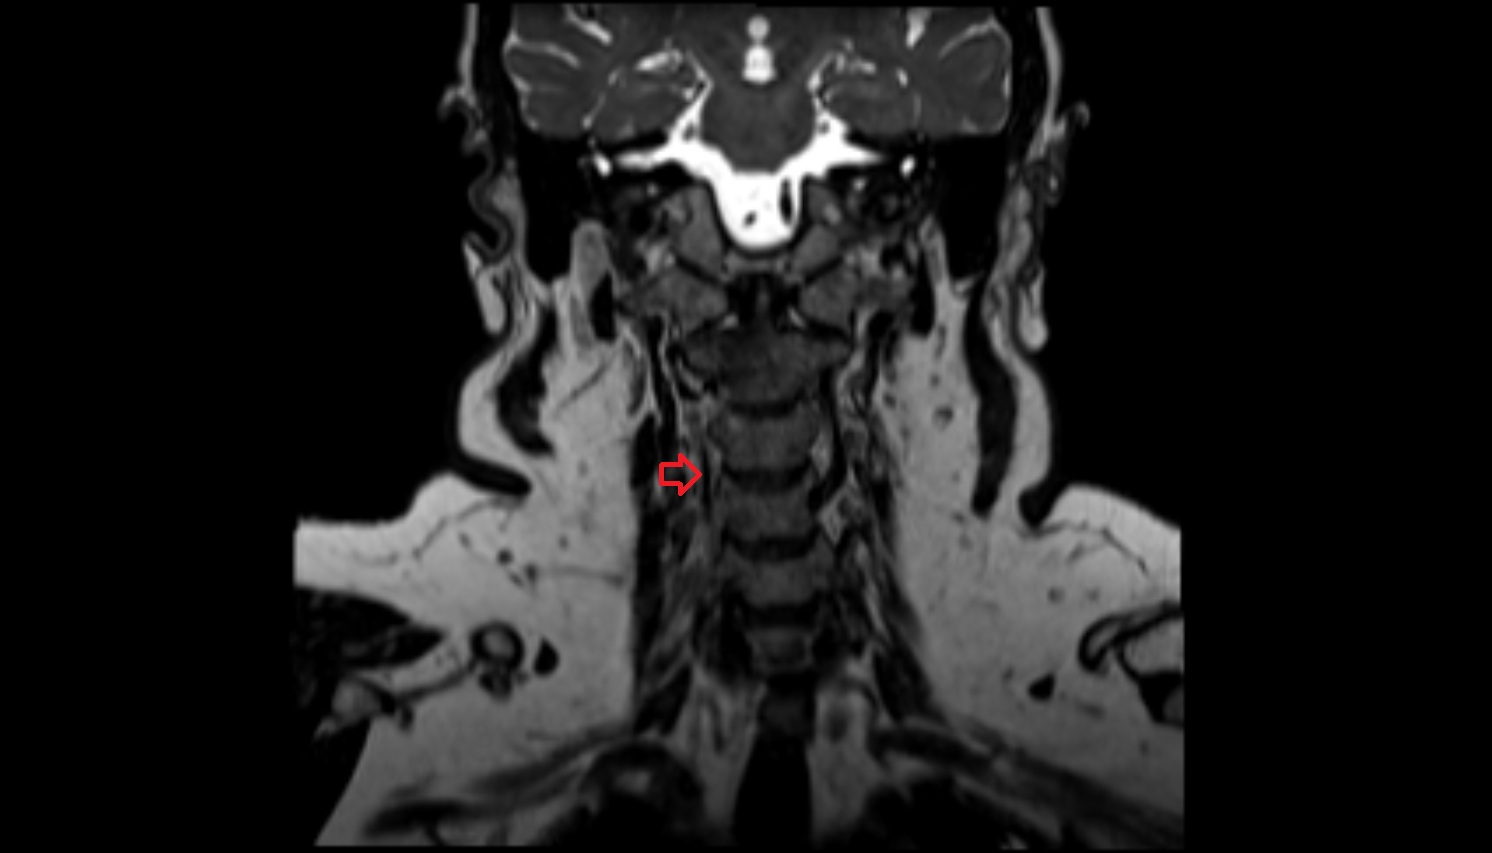

- Spinal cord

- Upper cervical spinal cord

- Cervical spinal nerve 1 (C1)

- Cervical spinal nerve 2 (C2)

- Cervical spinal nerve 3 (C3)

- Cervical spinal nerve 4 (C4)

- Cervical spinal nerve 5 (C5)

- Cervical spinal nerve 6 (C6)

- Cervical spinal nerve 7 (C7)